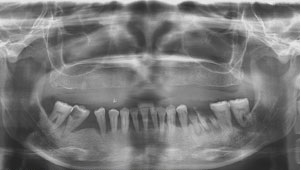

Nếu bạn bị viêm nha chu, thông thường có 4 loại điều trị căn bản thường được áp dụng: khẩn cấp, không phẫu thuật, phẫu thuật và duy trì. Điều trị không phẫu thuật có tỷ lệ áp dụng cao nhất, là bước điều trị đầu tiên trong bệnh nha chu, gồm 2 bước. Ở bước sơ khởi, nha sĩ sẽ đánh giá các yếu tố thuận lợi cho sự lưu giữ mảng bám, cản trở vệ sinh răng miệng và kiểm soát mảng bám vi khuẩn và loại bỏ các yếu tố đó bằng cách:

- Đánh giá và chỉ định răng cần nhổ (không thể giữ được).